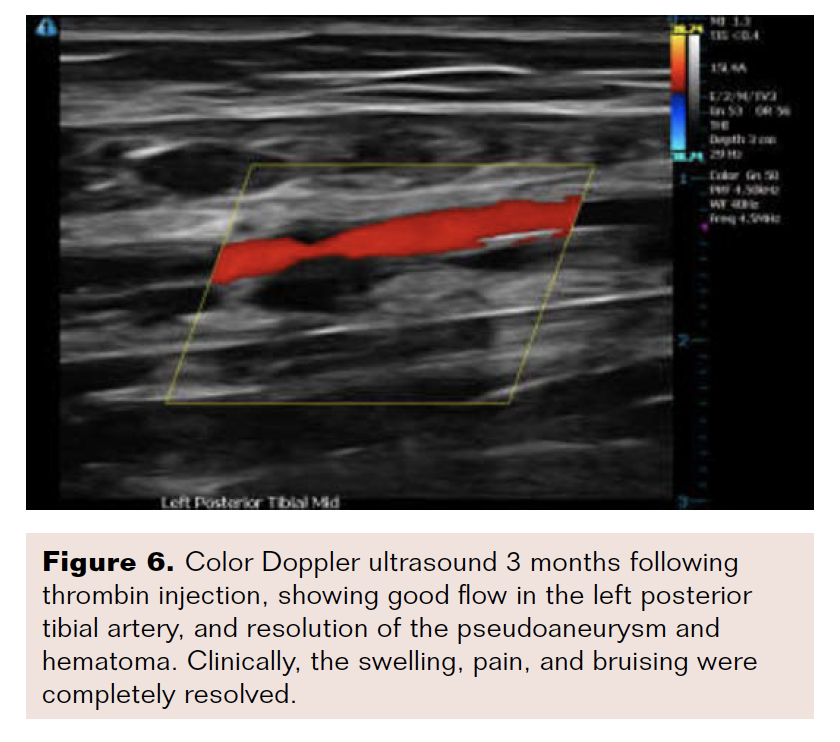

Two days after the procedure, the patient presented for follow-up with complaints of localized pain and mild swelling of his left leg. An arterial ultrasound showed no significant abnormalities, and the patient was sent home with non-steroidal anti-inflammatory drugs and a plan for close follow-up. One week later, the patient presented for his scheduled visit with worsening pain and swelling. On physical examination, there were new, tender ecchymoses noted in the region of the access site, along the inner sole of the foot, and in the area of the first three toes (Figure 1). Color Doppler ultrasound of the left leg showed a large pseudoaneurysm involving the PT (Figure 2). An attempt at ultrasound-guided compression yielded partial success, with thrombus involving only a small portion of the pseudoaneurysm. A decision to try ultrasound-guided thrombin injection was subsequently made.

The patient was placed in the supine position for 4 hours after the procedure. Follow-up ultrasound scans at 5, 15, 30, 60, 120, and 240 minutes after the procedure showed good distal flow in the left posterior tibial artery, with stable thrombosis of the sac, after which the patient was discharged home. Forty-eight hours later, follow-up ultrasound demonstrated a widely patent PT artery with no flow in the pseudoaneurysm (Figure 5). At 3-month follow-up, there was complete resolution of pain, swelling, and bruising, and the PT showed good flow on color Doppler ultrasound (Figure 6).